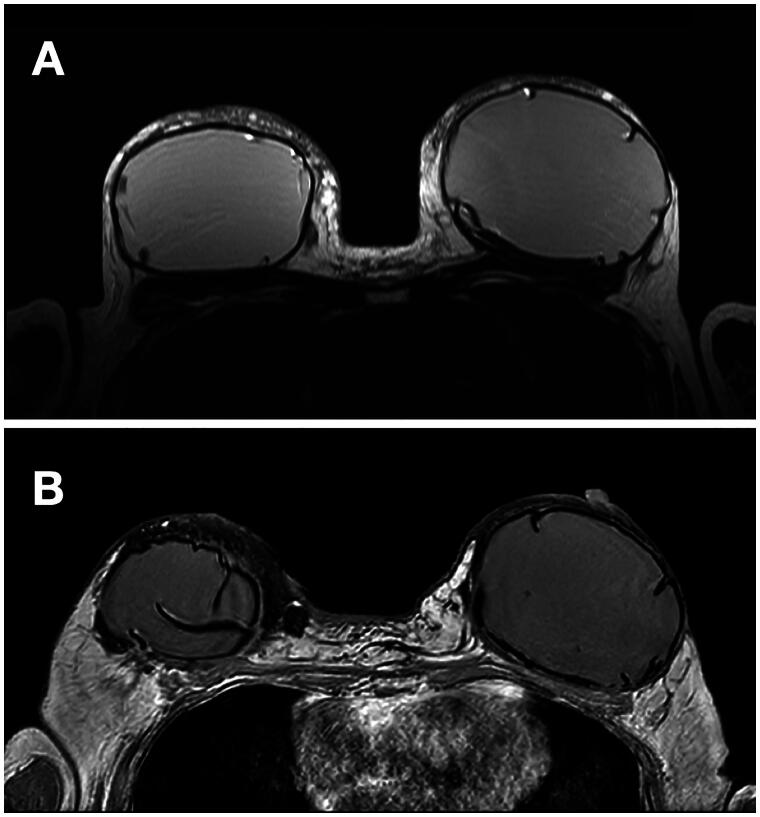

Silicone lymphadenopathy and granuloma formation can result from breast implants. A 71-year-old presented with implant rupture 30 years after a breast augmentation, causing left-sided silicone lymphadenopathy and extensive migration to the breast parenchyma and skin. Management included a mastectomy, lymph node resection, implant removal with complete intact capsulectomy, and latissimus-dorsi-based reconstruction.